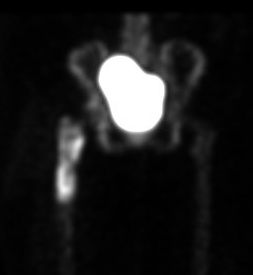

PET scan / [18F]Fluoro-2-deoxyglucose positron emission tomography (FDG-PET)

Kwee et al Eur J Nucl Med Mol Imaging 2008

- meta-analysis 11 studies and 600 patients

- 82% sensitive and 87% specific